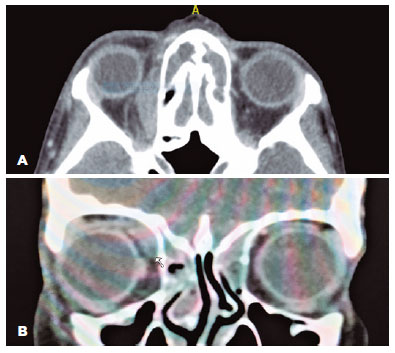

After 24 hours, the patient’s condition dramatically improved on medical therapy, and surgical intervention was deferred while keeping the patient on antibiotic therapy. Two days later, after cessation of the corticosteroid therapy, the symptoms recurred with gradual worsening of the pain, diplopia, and swelling. At this stage, magnetic resonance imaging (MRI) was ordered and revealed improvement of the sinusitis along with right superior oblique muscle and tendon enlargement and enhancement. A clear demarcation was observed between the muscle and the non-elevated medial orbital wall with no fluid collection (Figure 3). Hence, isolated right superior oblique myositis was diagnosed. At this stage, measurement of IgG4 level was ordered, and the result was unremarkable.

14-fig03.jpg)

In our report, the clinical presentation with the initial CT findings masqueraded the superior oblique myositis as a subperosteal abscess; hence, the case was labeled as such. The close approximity of the superior oblique muscle to the medial orbital wall with the intense inflammation made it difficult to identify distinct borders between the structures and misled the diagnosis to subperiosteal abscess. However, the dramatic response to the initial dexamethasone dose and the relapse after its effect has waned influenced our management plan, and further imaging confirmed the diagnosis of myositis. The use of systemic steroid in orbital cellulitis is controversial as the final outcomes are almost the same. Some authors recommend its use from the start to shorten the hospital stay and hasten the recovery, while others find it unsafe to suppress the patient’s immunity under an infectious etiology(9). In this case, it was advantageous to use a short-term systemic steroid therapy that helped us to diagnose superior oblique myositis.